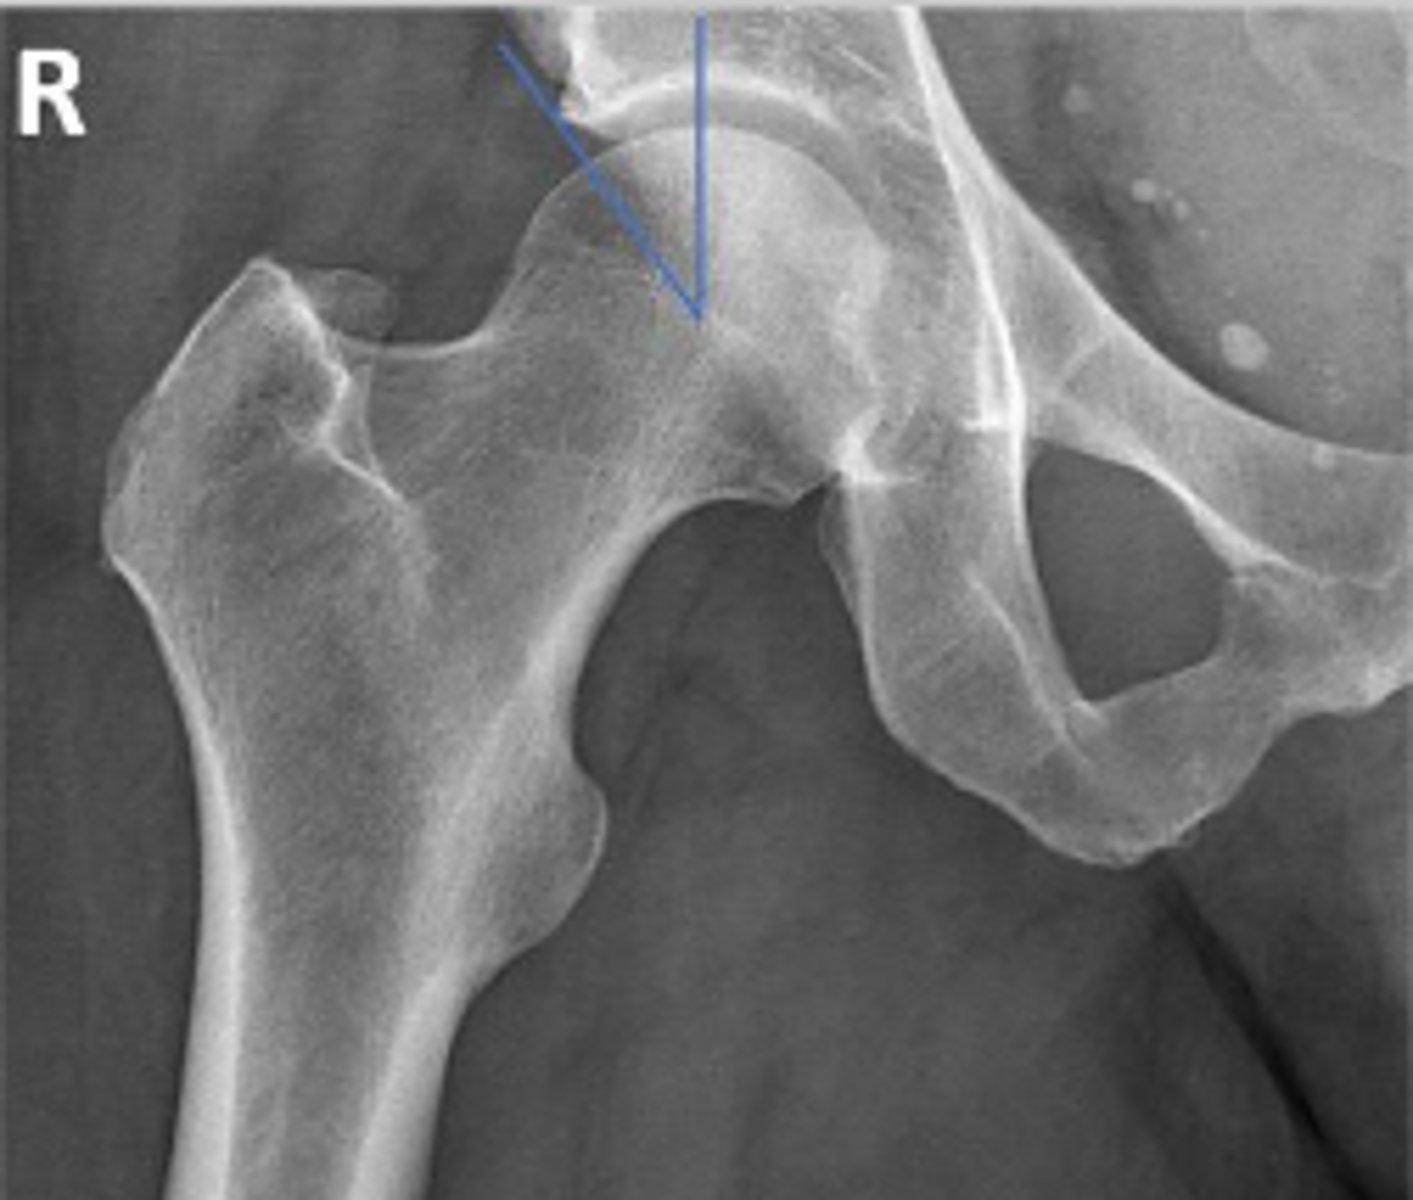

Posterior rim of the right acetabulum

What are the arrows pointing to?

Anterior rim of the right acetabulum

Lesser trochanter of the right femur

Greater trochanter of the right femur

Right posterior inferior iliac spine

Intertrochanteric line of the right femur

Right ischial tuberosity

Right iliopectineal line

What is the name of the assessment?

Right ilioischial line

Center edge angle

20-40 degrees

What is the normal range for this assessment?

A vertical line is drawn upwards from the center

of the head of the femur.

The second line is drawn from the center of the femur head to the outer superior-lateral aspect of the acetabulum

What are the osseous landmarks for this assessment

No (normal measurement is 20-40 degrees)

Is the measurement within normal limits?